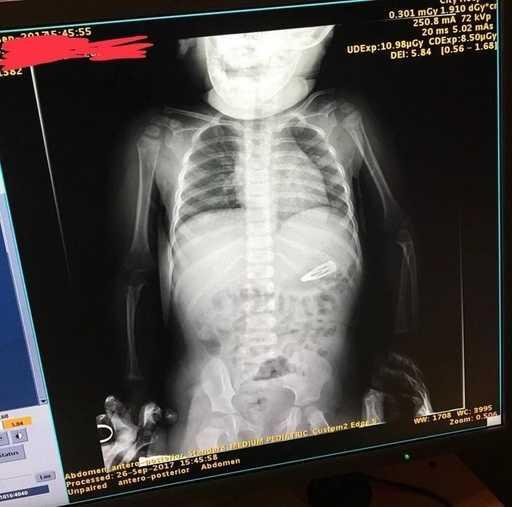

10. 「我朋友的儿子吞了雪花?」

一些奇怪的X光照片,看完整个人都不好了……-10.jpg